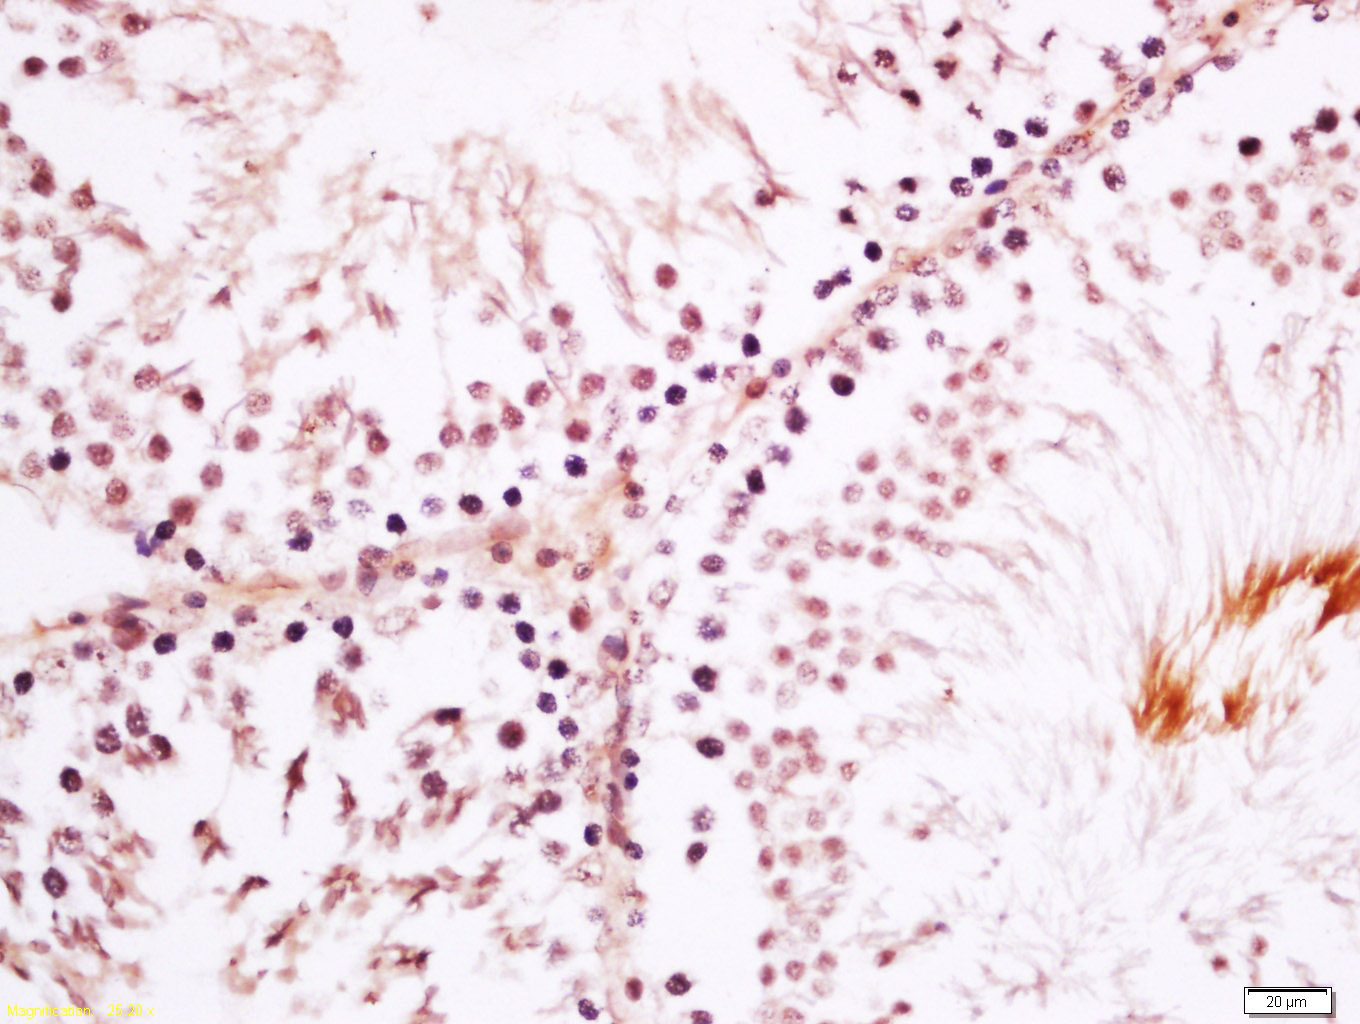

Tissue/cell: rat testis tissue; 4% Paraformaldehyde-fixed and paraffin-embedded; Antigen retrieval: citrate buffer ( 0.01M, pH 6.0 ), Boiling bathing for 15min; Block endogenous peroxidase by 3% Hydrogen peroxide for 30min; Blocking buffer (normal goat serum,C-0005) at 37℃ for 20 min; Incubation: Anti-SRGAP1 Polyclonal Antibody, Unconjugated(bs-10671R) 1:200, overnight at 4°C, followed by conjugation to the secondary antibody(SP-0023) and DAB(C-0010) staining

Tissue/cell: rat brain tissue; 4% Paraformaldehyde-fixed and paraffin-embedded; Antigen retrieval: citrate buffer ( 0.01M, pH 6.0 ), Boiling bathing for 15min; Block endogenous peroxidase by 3% Hydrogen peroxide for 30min; Blocking buffer (normal goat serum,C-0005) at 37℃ for 20 min; Incubation: Anti-SRGAP1 Polyclonal Antibody, Unconjugated(bs-10671R) 1:200, overnight at 4°C, followed by conjugation to the secondary antibody(SP-0023) and DAB(C-0010) staining